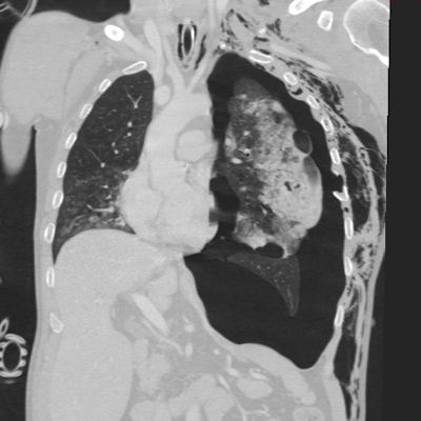

In this hemodynamically unstable patient, what is your first intervention after seeing this CT?

a) Left needle thoracostomy

b) Start blood transfusion

c) Pericardiocentesis

d) Mechanical ventilation with high PEEP

e) Intubation

A